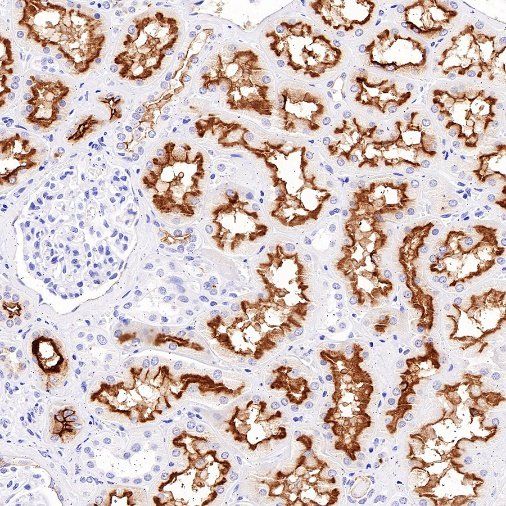

Immunohistochemistry

IHC shows positive staining in paraffin-embedded human kidney. Anti-MDR1/ABCB1 antibody was used at 1/1000 dilution, followed by a HRP Polymer for Mouse & Rabbit IgG (ready to use). Counterstained with hematoxylin. Heat mediated antigen retrieval with Tris/EDTA buffer pH9.0 was performed before commencing with IHC staining protocol.